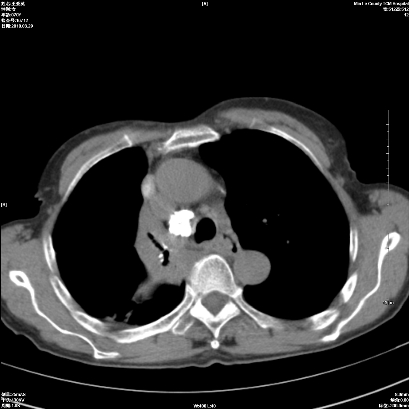

标题: CT25424:女性,70岁,胸闷、咳嗽月余。 [打印本页]

标题: CT25424:女性,70岁,胸闷、咳嗽月余。

右肺上叶支气管开口阻塞,上叶呈不均匀致密影,右肺中下叶内见斑片状密度增高影,上叶见钙化点,纵隔内见钙化淋巴结,桶状胸,右下肺动脉增粗,残根征,意见:1.右肺中心性肺癌;2.右肺陈旧性结核;3.肺心病。

1 右肺门占位伴上叶不张 2 有肺多发感染 3 肝脏转移? 建议增强

考虑右肺中心型肺癌并上叶不张

1、右侧中央型肺癌伴右肺上叶不张建议支气管镜检   2、右肺中叶及下叶陈旧性病灶   3、肝内多发低密度影,肝内多发转移不除外,建议ct增强!

1)考虑右肺中央型肺癌伴右肺上叶肺不张,右肺门淋巴结转移;建议行支纤维镜检查。2)右肺中叶、下叶及左肺上叶舌段感染性病变。3)肝内多发低密度影,不排除转移瘤可能;建议行ct增强扫描检查。

ct所见:右肺上叶肺不张,呈软组织密度影向肺门区聚拢,其内可见含气段支气管及细支气管影,病灶内尚可见钙化结节。右肺上叶支气管狭窄,段支气管壁可见钙化。右肺下叶背段、右肺中叶见不规则小片絮状影及纤维条索影,形态较僵硬。右肺中叶胸膜旁可见多个小结节影。纵膈内见钙化淋巴结。

分析:右侧胸廓及右肺体积缩小,说明病变时间比较长了,应该是有数年的时间了,如果是短期内出现的肺不张,只会引起纵膈向患侧移位,而不会引起胸廓的塌陷。不张的肺组织内可见含气支气管影,说明右肺上叶支气管没有完全中断,只是狭窄。右肺中叶、下叶散在不规则病灶,部分呈纤维化改变。纵膈内的淋巴结大部分钙化。因此,本例给我的感觉良性病变的可能是大。

结论:考虑右肺上叶支气管内膜结核合并右肺上叶肺不张;右肺中叶、下叶陈旧性肺结核改变。